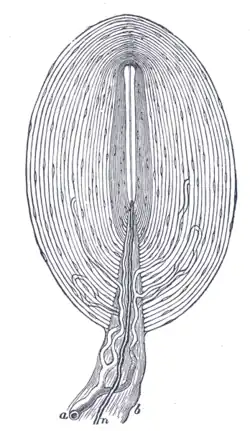

Rycina przedstawiająca przekrój ciałka blaszkowatego.

Ciałko blaszkowate, ciałko Vatera-Paciniego – rodzaj szybko adaptujących się, najbardziej skomplikowanych[1] mechanoreceptorów[2], wrażliwych na nacisk i wibracje[1][3]. Ciałka przypominają małe, białe cebulki[3]; różnią się wielkością, ale są wystarczająco duże, by móc dostrzec je „gołym okiem[2] (średnica ok. 3 mm)[3]. Zbudowane są z koncentrycznie ułożonych warstw fibroblastów[1], wypełnione są płynem[2], a w ich rdzeniach znajduje się pojedynczy, niemielinowany akson[1][2] i jego komórki Schwanna[1].